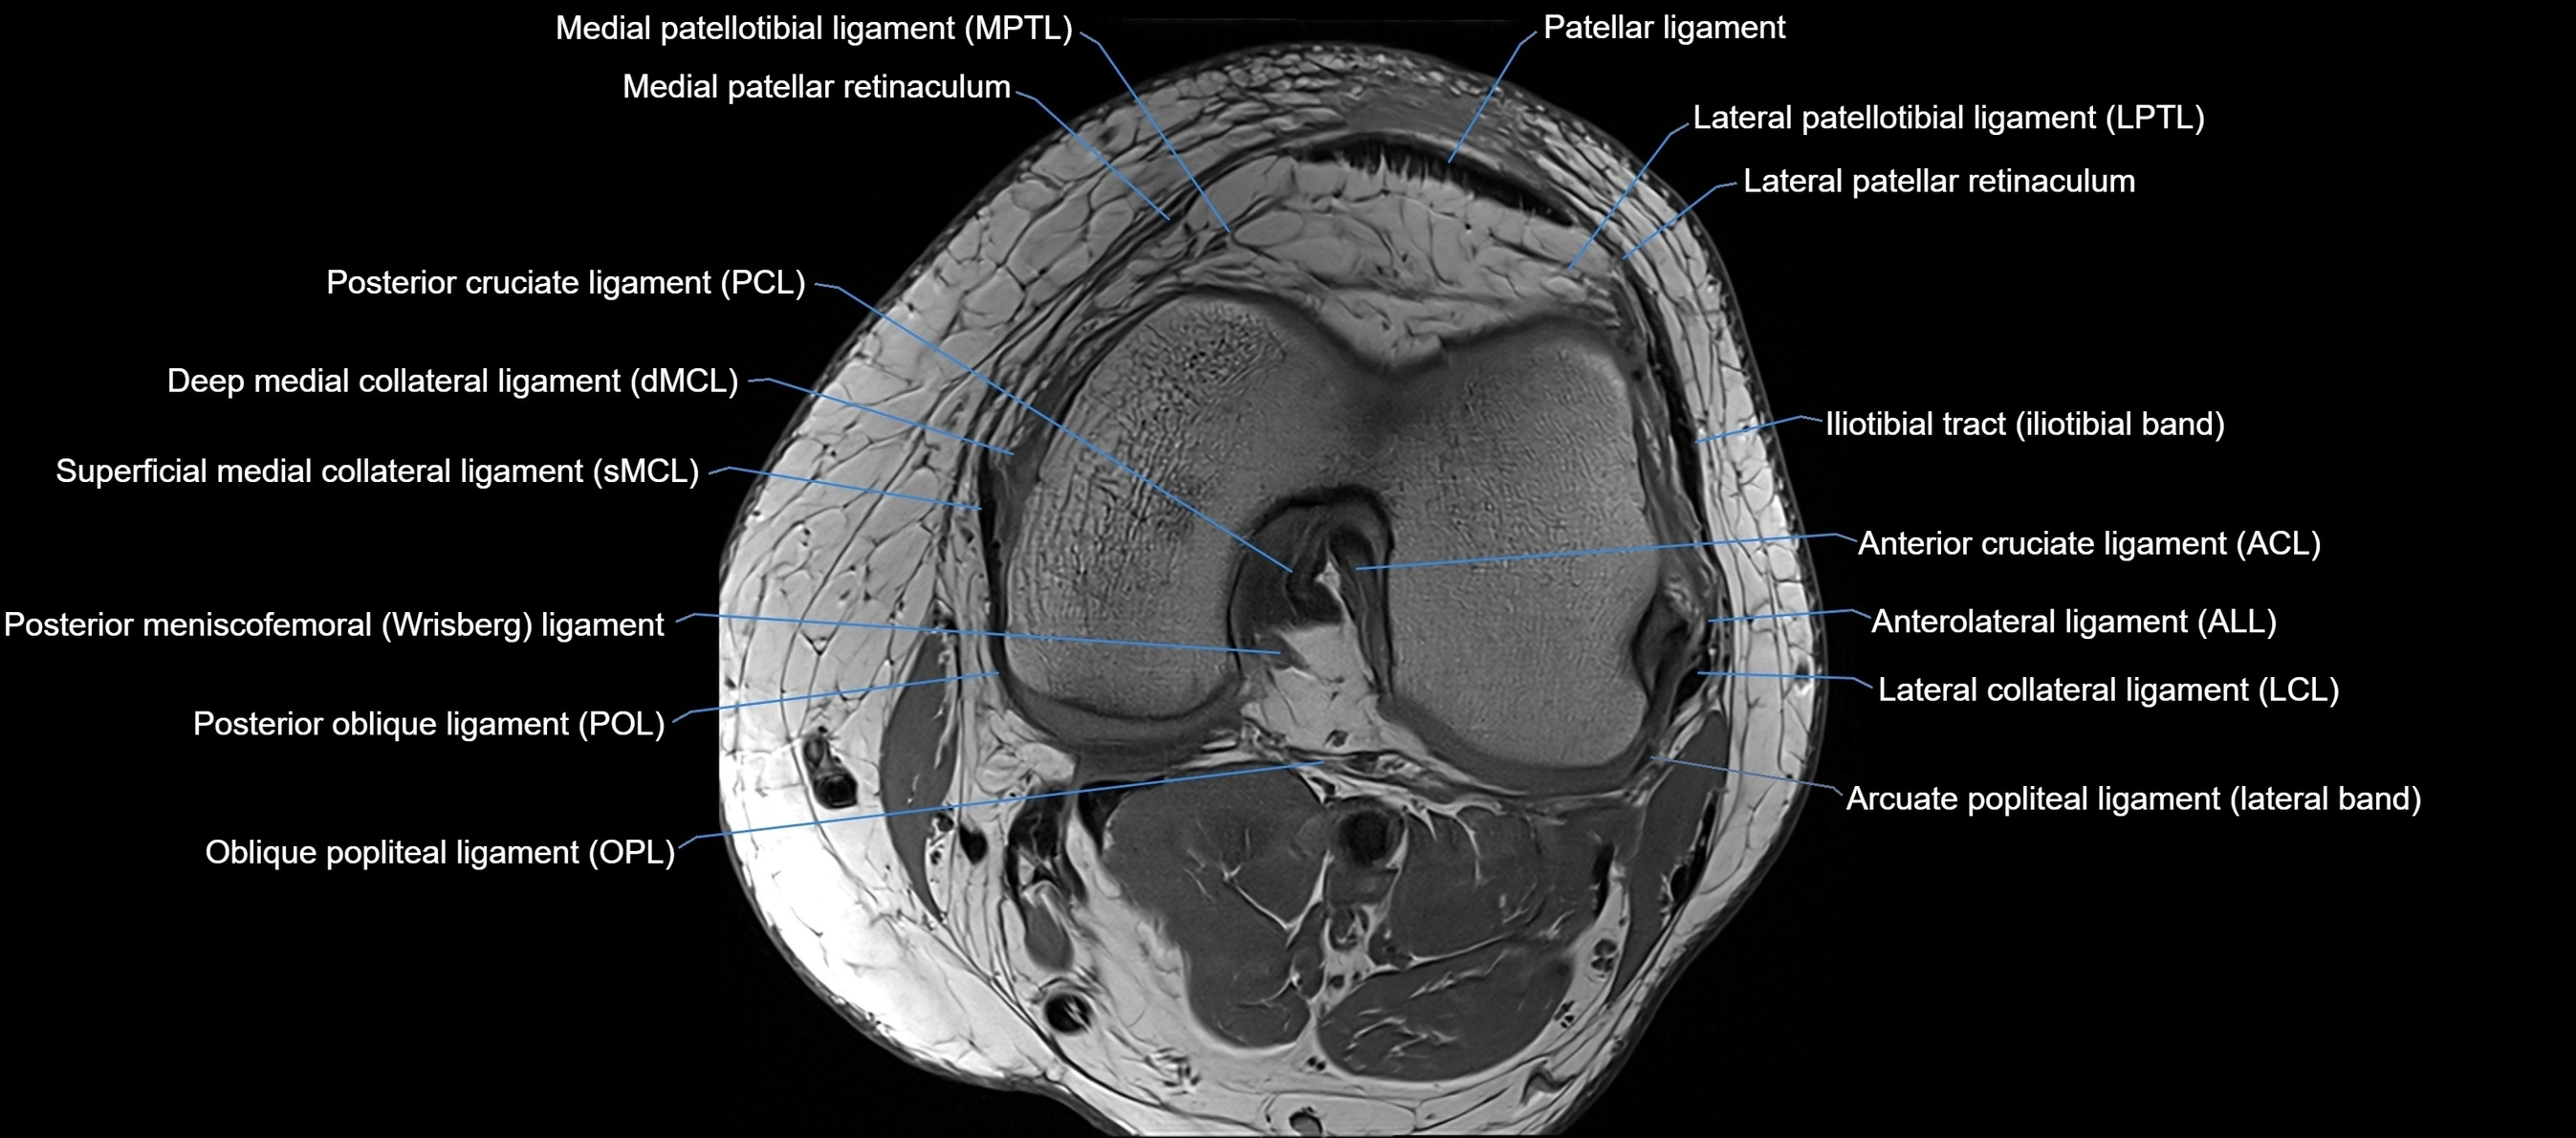

MRI Appearance

T1-weighted images:

• Normal ACL appears as a low-signal band-like structure crossing the intercondylar notch

• Surrounded by intermediate signal synovial fluid and fat planes

T2-weighted images:

• Normal ACL remains low signal

• Partial or complete tears appear as discontinuity, increased signal, or fiber laxity

STIR (Short Tau Inversion Recovery):

• Normal ACL shows dark low signal

• Acute injury shows bright hyperintensity due to edema and hemorrhage

Proton Density Fat-Saturated (PD FS):

• Normal ACL: dark, low-signal band

• Tears: bright intraligamentous hyperintensity, discontinuity, or abnormal course

MRI images

image